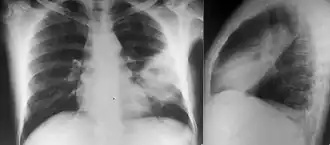

Various imaging modalities can also help with the diagnosis of melioidosis. In acute melioidosis with the spreading of the bacteria through the bloodstream, the chest X-ray shows multifocal nodular lesions. It may also show merging nodules or cavitations. For those with acute melioidosis without the spread to the bloodstream, chest X-ray most commonly shows upper lobe consolidation or cavitations.[10] In chronic melioidosis, the slow progression of upper lobe consolidation of the lungs resembles tuberculosis.[10] For abscesses located in other parts of the body apart from the lungs, especially in the liver and spleen, CT scan has higher sensitivity when compared with an ultrasound scan. In liver and splenic abscesses, an ultrasound scan shows "target-like" lesions while a CT scan shows "honeycomb sign" (abscess with loculations separated by thin septa) in liver abscesses.[10] For melioidosis involving the brain, MRI has higher sensitivity than a CT scan in diagnosing the lesion. MRI shows ring-enhancing lesions for brain melioidosis.[10]